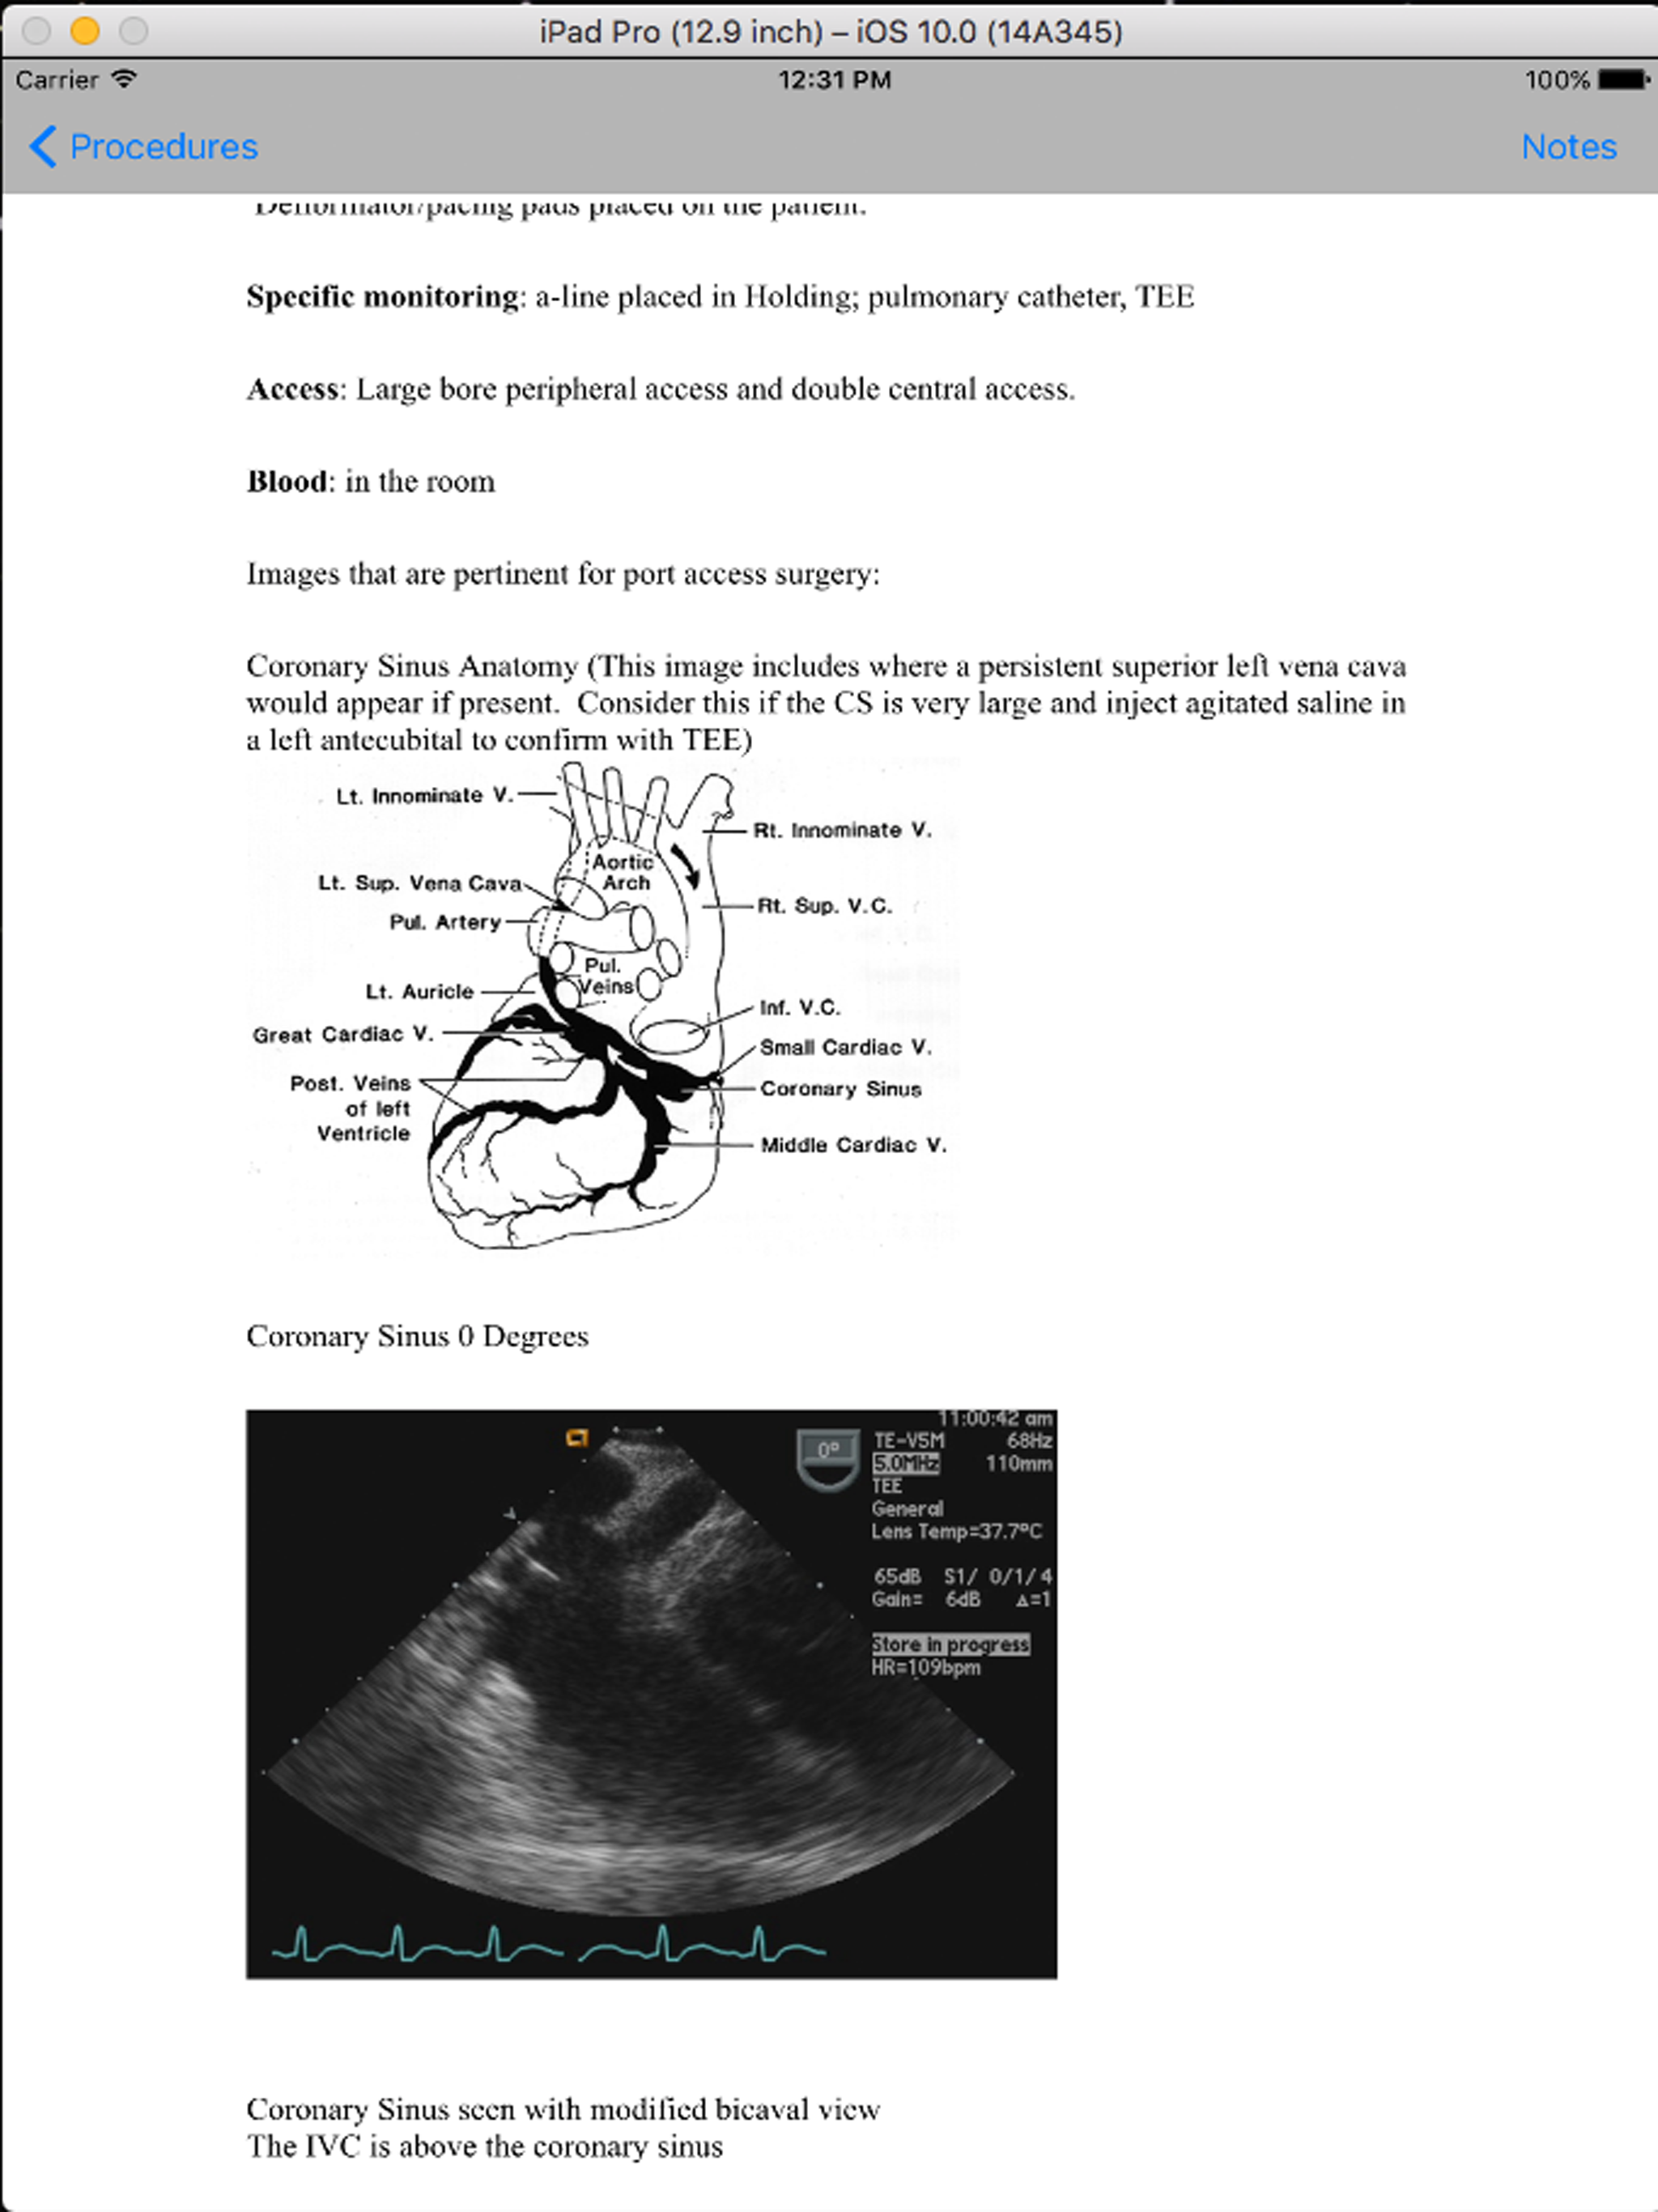

Anesthesia 411 is a collection of more than 125 of the most common cases seen by an anesthesiologist. This is not a didactic manual that goes over diseases, theory and physiology. Rather, this is a simple guide when one needs information fast. Using a simple format, it will tell you what you need to set up your room in about 60 seconds. It will guide you on the IV access, drugs, monitors and special equipment you will need to do this case. It will go over pre-op, intra-op and post-op issues germane to the case. A detailed section has been added for those doing minimally invasive port access AVR and MVR cases. This includes TEE images showing CS catheter and pulmonary vent placement. It includes correct and incorrect placement fluoroscopy images for the coronary sinus catheter. Tips are also given from experts on how to know the CS is in the correct position. Don't be intimidated by a case you have never done. Anesthesia 411 will give you the information you need to get up to speed in seconds. Whether you are a resident, CRNA or junior attending, this guide is a must when you need the 411.